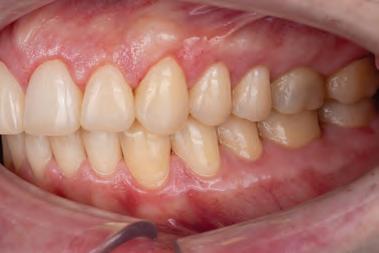

A 31-year-old woman presented with cosmetic concerns regarding her smile and requested a conservative enhancement. After clinical and radiographic analysis, digital 35mm photographs were taken and reviewed by the restorative clinician, technician, and surgeon (Fig 1). A digital impression was taken of the maxillary and mandibular arches using an intraoral scanner (Trios 3, 3Shape; Fig 2), and a smile design was developed with NemoSmile Design 3D software (Nemotec; Fig 3a). This allows for a facially driven smile frame to be created using reference lines of facial and smile proportions and natural teeth shapes and textures from the digital library (Fig 3b).

After developing the simulated mock-up, a 3D-printed resin model was created using CAD software (Fig 4a), and a clear PVS matrix (Exaclear, GC America) was fabricated to replicate the printed diagnostic wax-up using a nonperforated tray (Fig

Fig 1 Preoperative clinical views of a 31-year-old woman presenting with diastemas and limited tooth visibility. (top) Portrait. (center row) Intraoral views. (bottom row) Smile.

4b). This matrix was used to create an intraoral motivational mock-up with bis-acryl composite (Luxatemp Ultra, DMG). This additive mock-up provides the interdisciplinary team with an intraoral translation for evaluation (Fig 5). Upon evaluation of the digital smile frame and the clinical translation, it was determined that multiple esthetic and restorative requirements were necessary for an optimal biologic framework, and the interdisciplinary team determined the best sequence for these procedures. The patient was presented with the interdisciplinary treatment possibilities that included restoring the maxillary anterior teeth and premolars with a minimally

invasive preparationless procedure or with less conservative veneer preparations. The restorative materials discussed included injectable resin composites and ceramic (ie, feldspathic, pressable, machinable). For an optimal biologic framework and health, it was determined that connective tissue grafting would be necessary for treatment of the recessiontype defects on the maxillary left central and lateral incisors, canine, and premolars. The patient opted for the conservative preparationless composite veneers using the injectable resin technique followed by a connective tissue surgical procedure using the tunneling technique.